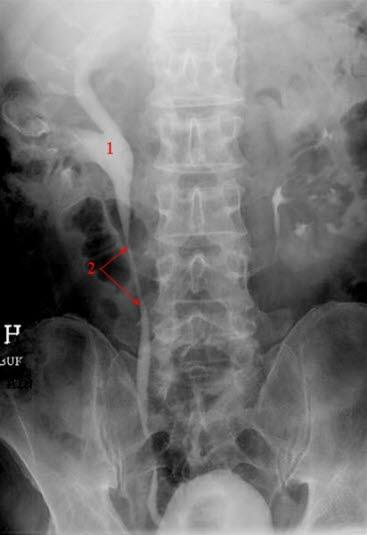

Ved hydronefrose foreligger en utvidelse av samlesystemet. Denne utvidelsen skyldes i de fleste tilfeller et hinder i urinveien nedenfor nyrebekkenet. Konsekvensen blir at urin hoper seg opp ovenfor hindringen, noe som øker trykket i den øvre delen av urinveien, også i nyrebekkenet. Vedvarer trykket lenge nok, vil nyrevevet kunne presses sammen og nyrefunksjonen vil kunne svekkes.

Hydronefrose skyldes en avløpshindring i urinveiene. En slik hindring kan for eksempel være en forstørret prostatakjertel eller en forsnevring i den ene eller begge urinlederne. Dette vil føre til økt trykk i de øvre urinveiene ovenfor det trange partiet, slik at nyrenes samlesystem utvides.

Risikofaktorer er enhver tilstand som kan medføre et passasjehinder for urinen. De vanligste årsakene er nyrestein, gynekologiske tilstander, forsnevringer i urinrør eller urinleder, prostatasykdom, svulster, eller tilbakestrømming av urin fra blæren (refluks). Medfødte misdannelser og sammenpressing av urinveiene forårsaket av infeksjon/hevelse i naboorganer kan også være forklaringen.